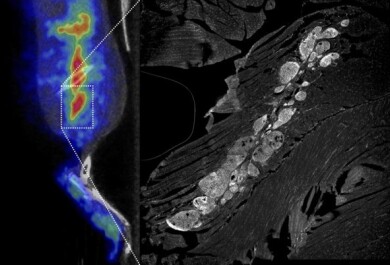

Tutkimukseen rekrytoitiin THL:n väestöpohjaisen Terveys 2000 -tutkimuksen perusteella 60 noin 70-vuotiasta tutkittavaa, joilla ei ollut diagnosoitu diabetesta tai muistisairautta. Puolella tutkittavista oli alentunut ja puolella normaali insuliiniherkkyys vuonna 2000.  Tutkittaville tehtiin vuosina 2014–2016 tarkat neuropsykologiset testit, aivojen magneettikuvaukset ja aivojen amyloidikertymistä kertovat positroniemissiotomografia (PET) -kuvaukset.

Aivojen amyloidikertymien ja hitaamman prosessointinopeuden väliltä löydettiin yhteys, mutta vastaavaa yhteyttä ei löydetty aivojen verenkiertoperäisten muutosten ja neuropsykologisissa testeissä suoriutumisen väliltä.